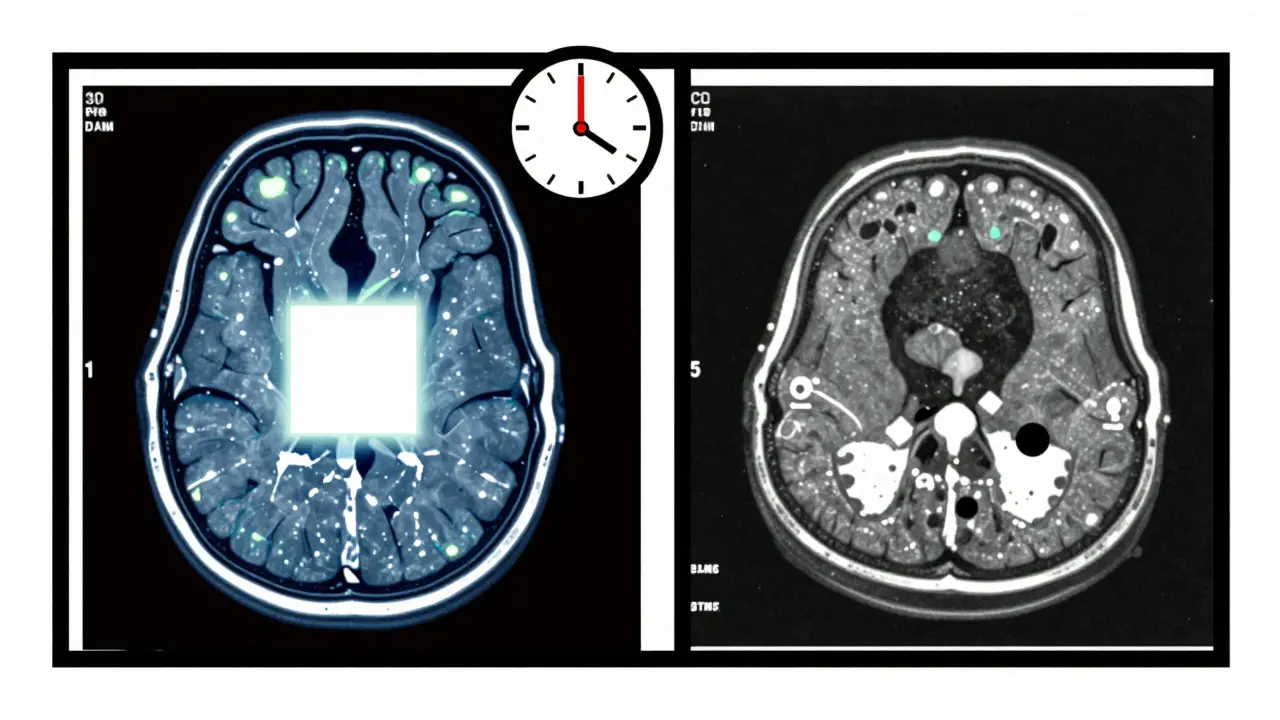

Comparaison d’un cerveau sain et d’un cerveau avec lésions, en style géométrique abstrait.

Comparaison abstraite IRM et TDM en blocs colorés, avec horloge et lignes de grille.